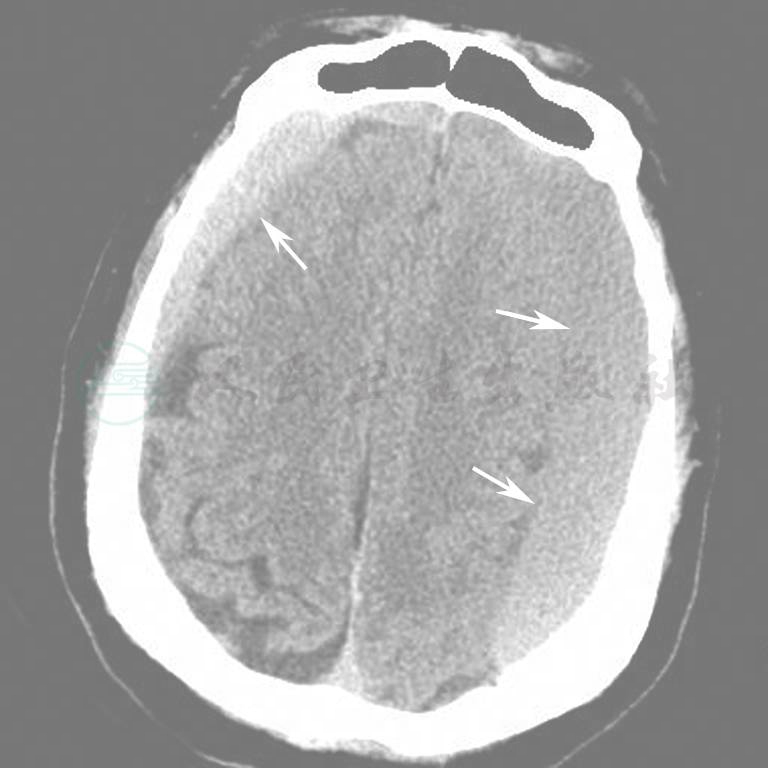

图11  双侧颅内出血(硬膜下)

图12  右侧颅内出血(硬膜下)

图13  右侧颅内出血(硬膜下)

图14  右侧慢性硬膜下出血